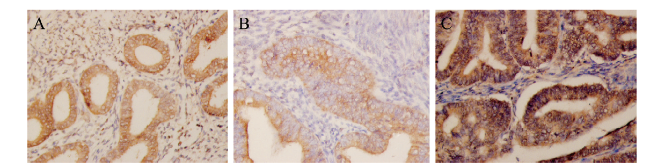

Cyclin D3在正常子宫内膜、单纯型子宫增生内膜和EMC的组织中均呈现阳性表达。其主要在腺细胞或腺癌细胞中表达明显,位于细胞浆中,呈淡黄或棕黄色,基质细胞中呈现阴性表达或弱表达,见图1

图1 不同子宫内膜组织中Cyclin D3的表达

A:正常子宫内膜组织中Cyclin D3的阳性表达(×100);B:单纯型子宫内膜增生组织中Cyclin D3的阳性表达(×200);C:EMC组织中Cyclin D3的阳性表达,主要分布在腺癌细胞胞浆中(×200)

12例正常子宫内膜组织中,有4例为Cyclin D3阳性表达(2例为中表达,2例为高表达),阳性表达率为33%(4/12)。13例单纯型子宫内膜增生组织中,有9例为Cyclin D3阳性表达(6例为中表达,3例为高表达),阳性表达率为69%(9/13)。45例子宫内膜样腺癌组织中,35例为Cyclin D3阳性表达(24例为中表达,11例高表达),阳性表达率为78%(35/45)。Cyclin D3在正常子宫内膜、单纯型子宫内膜增生及子宫内膜样腺癌中的表达比较差异有统计学意义(χ2 = 8.687,P = 0.013),其中子宫内膜样腺癌组高于正常子宫内膜组(χ2 = 8.661,P = 0.003)。